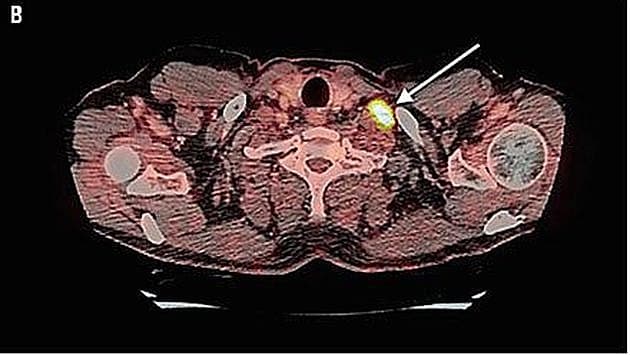

PET-CT i aksialt snit. Pilen viser den FDG-positive lymfeknude på halsen. Ill. fra artiklen.